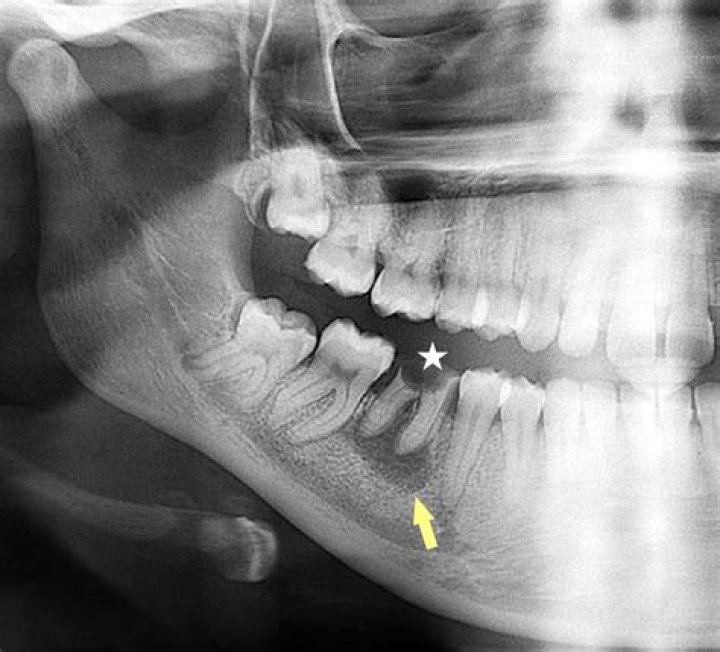

Intraoral X-rays or a 3-D cone beam scan of the affected area can be used to obtain radiological images and confirm diagnosis of cysts in the periapical area. Circular or ovoid radiolucency surrounding the root tip of approximately 1-1.5 cm in diameter is indicative of the presence of a periapical cyst.

Periapical cysts, also known as radicular cysts, are the most frequent cystic lesion related to teeth (see mandibular lesions) and result from infection of the tooth. On imaging, they generally appear as a round- or pear-shaped, unilocular, lucent lesion in the periapical region, usually measuring <1 cm.

Histologically, radicular cysts can be categorized into pocket and true cyst. The radicular cyst appears as an osteolytic periapical radiolucent lesion around the apex of an endodontically involved tooth on conventional radiography and cone beam computed tomography.

Location. In most cases, the epicenter of a radicular cyst is located approximately at the apex of a nonvital tooth (Fig. 21-1). It occasionally appears on the mesial or distal surface of a tooth root at the opening of an accessory canal or infrequently in a deep periodontal pocket.

Periapical cysts result from infection of the tooth, which spreads to the apex and into the adjacent bone. This leads to apical periodontitis, granuloma formation and eventual cyst formation. These cysts are therefore centered on the apex of the tooth and tend to be small, most <1 cm.